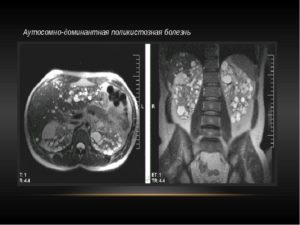

Проводится с кистами и гнойно – деструктивными заболеваниями почки (карбункул и абсцесс почки), гидронефрозом, поликистозом и туберкулезом. Основное – это использование рентгенологических, УЗИ, КТ и МРТ.

Для диагностики распространенности процесса показано выполнение КТ, МРТ, рентгенографии и рентгеноскопии легких, УЗ печени и забрюшинных лимфоузлов, рентгенографии и сцинтиграфии костей скелета.